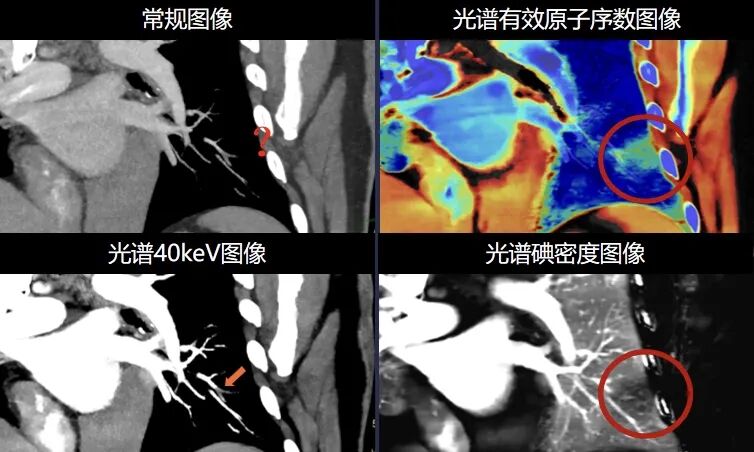

全新“逆向诊断”精准诊断肺栓塞

皓克CT对于每一个检查的患者都可以提供常规以及光谱多参数数据,这使得医生可以根据有效光谱原子序数图,碘密度图直接判断肺功能(肺灌注)是否存在异常;进而精准诊断肺栓塞,使得病患可以及时得到相应的治疗,挽救生命,避免并发症。